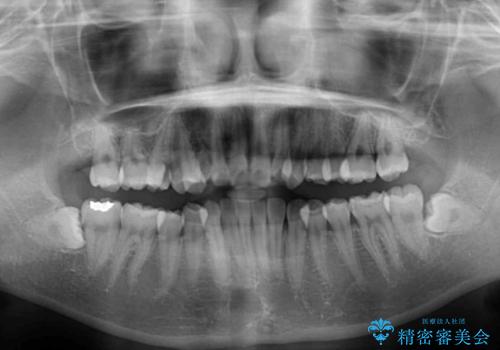

- 前歯のクロスバイトや残存している乳歯を気にして来院された患者様です。

上顎骨の幅が下顎骨よりも小さいので、拡大装置により骨幅を広げて上下関係を改善し、その後インビザラインにて歯並びを整えることとしました。

上下の骨幅を改善したことで、スムーズに歯列矯正を行うことができました。